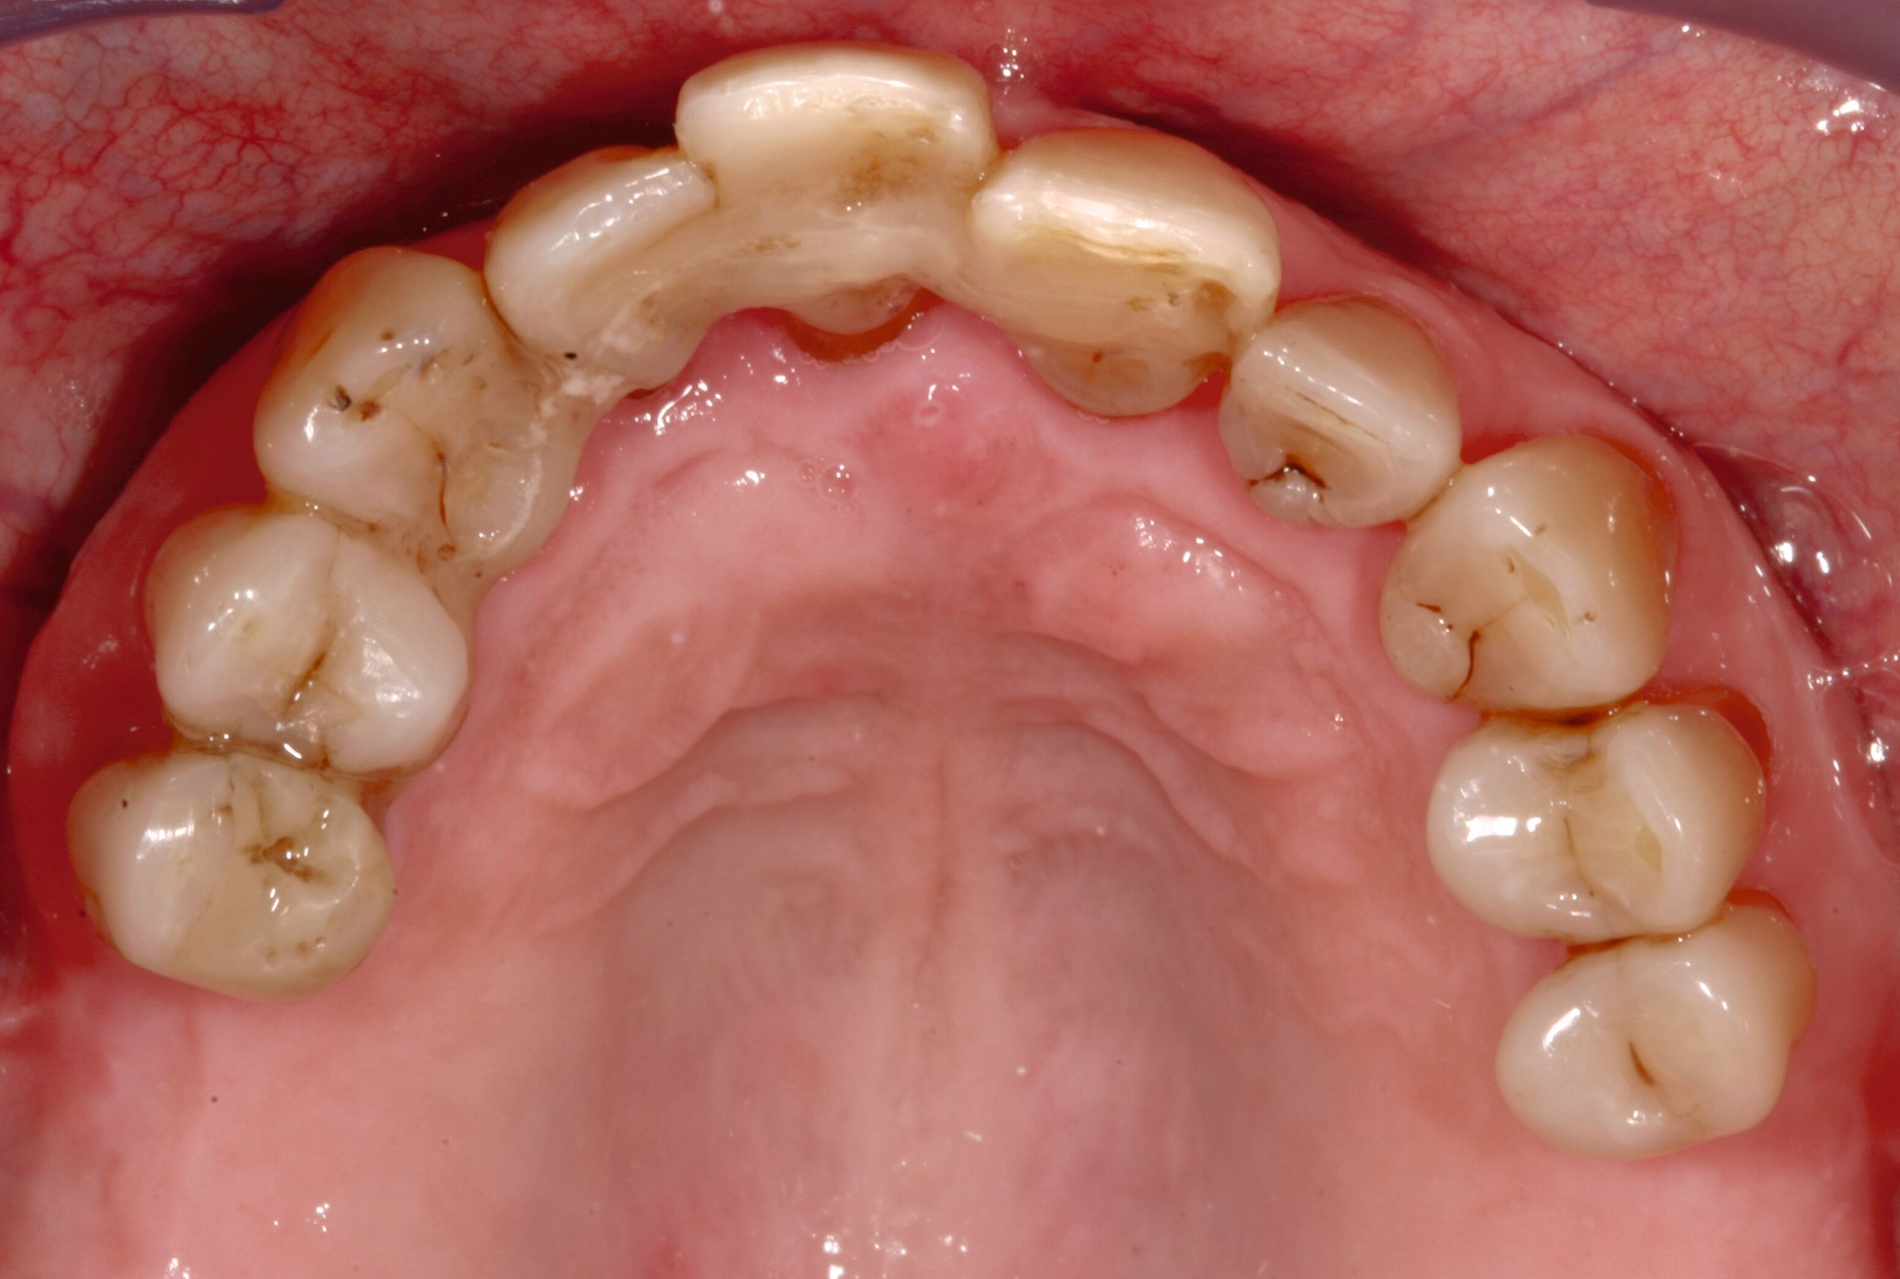

Auch wenn aufgrund der knöchernen Ausgangssituation Implantate im posterioren Bereich des Oberkiefers durchaus hätten inseriert werden können, wurde bei der Patientin bewusst die Entscheidung für eine Pfeilervermehrung in den Bereichen Eckzahn und erste Prämolaren getroffen (Abbildung 17). Die Patientin war bereits einige Jahre an eine abnehmbare Versorgung im Oberkiefer gewöhnt und hatte aufgrund einer rheumatoiden Arthritis eine jahrzehntelange Cortison-Anamnese sowie eine Einschränkung der manuellen Geschicklichkeit. Diese Faktoren sprachen für die erneute Versorgung mittels einer abnehmbaren Versorgung und einer Implantatinsertion im eher anterioren Bereich.

Die prothetische Versorgung erfolgte mittels Teleskopen auf dem natürlichen Pfeilerzahn 13 und den Implantaten 14, 23 und 24 (Abbildungen 18 und 19) sowie einer abnehmbaren zahn-implantatgestützen schleimhautgetragenen Prothese (Abbildungen 20 und 21). Die Patientin konnte über 20 Jahre nachuntersucht werden. Der parodontale Zustand erwies sich bei einem Nachsorgeintervall von anfangs sechs Monaten und danach mit unregelmäßigen Nachuntersuchungen – bedingt durch Alter und Anreise – als stabil. Der Zahn 13 musste aufgrund einer Sekundärkaries 2022 entfernt werden und die Prothese wurde anschließend erweitert. Bis zu diesem Zeitpunkt ergab sich prothetisch, bis auf eine Unterfütterung und Verblendungsreparatur, kein nennenswerter Nachsorgebedarf. Weitere Orthopantomogramme wurden in jüngerer Vergangenheit nicht erstellt, da dafür keine rechtfertigende Indikation vorlag.